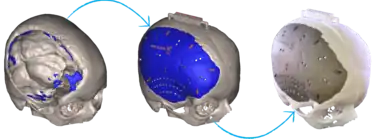

Diagram of workflow describing the basic process of 3D-printing an implant for the skull. Notice the use of the advanced computer software to create a 3-dimensional rendering of the part of the skull that will be printed. The rightmost photo depicts the 3D-printed implant placed on the actual skull.

3D-printed implants

3D-printing leverages the power of computer rendering of advanced imaging to tailor implants to each patient, which can then be used to create a physical realization of that implant to use in that individual's surgery.[18][19] 3D-printing of medical devices was first used in the 1990s for dental implants and custom prosthetics but has since been used for various bones and organs such as urinary bladders.[20][21][22]